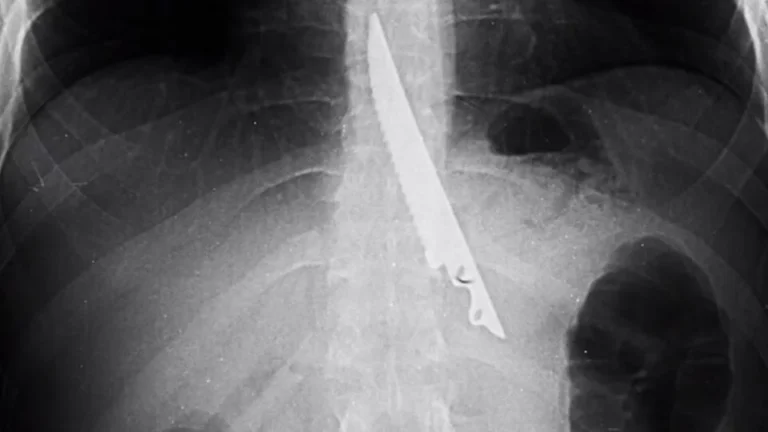

Moskvadan olan bir nəfər kabab dadarkən təsadüfən 20 santimetrlik bıçağı udub. Subyekt.az Ren Tv-yə istinadən xəbər verir...